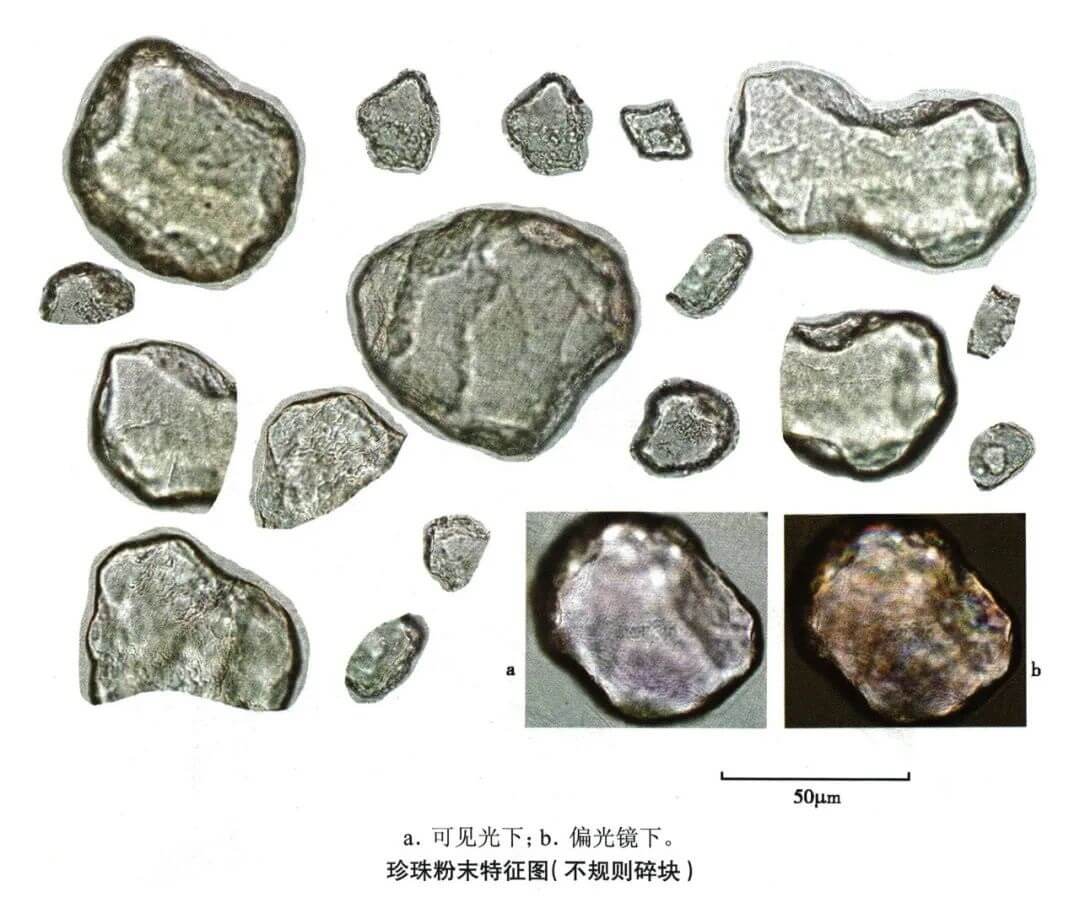

珍珠

| 珍珠 |

|---|

| 【参考标准】 《中国药典》2020年版 一部 |

| 【显微鉴别】 本品粉末类白色。不规则碎块,半透明,具彩虹样光泽。表面显颗粒性,由数至十数薄层重叠,片层结构排列紧密,可见致密的成层线条或极细密的微波状纹理。 |

| 【显微重点】 不规则碎块由数至十数薄层重叠,片层结构排列紧密。 |

| 【图谱来源】 《中药成方制剂显微图典》 |